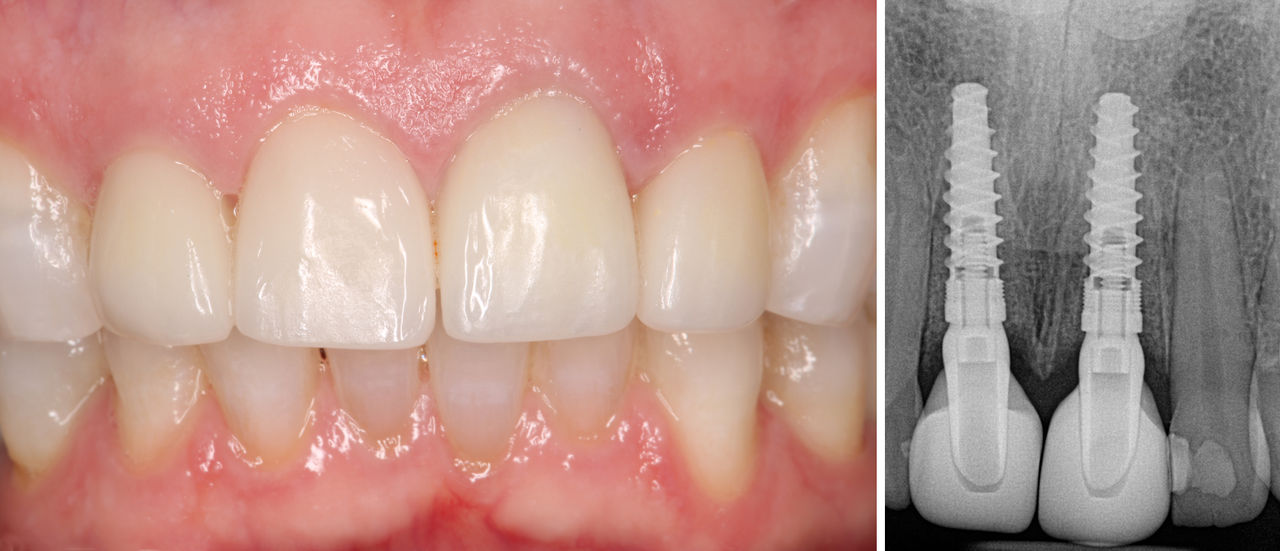

The patient left the surgical appointment in very good spirits after initially presenting for treatment in a distraught state. After four months, she returned so I could assess the healing of the implant sites and the integration of the Hahn Tapered Implants. Excellent soft tissue health and contours were evident around the provisional crowns, and radiography revealed excellent bone levels around the Hahn Tapered Implants.

Positive results after four months of the implant placement

Four months after implant placement, the patient exhibited excellent tissue and bone health, and the implant sites were ready to restore.

The implant crowns were tried in and then cemented over the custom abutments. Because the position of the gingiva was maintained throughout treatment with the immediate provisional crowns, as well as the custom fit and margins of the custom abutments, the final restorations exhibited lifelike emergence profiles. The patient was extremely happy with the final outcome, which improved her smile in addition to restoring function. She was especially pleased that she was able to have fixed teeth throughout treatment and remarked that she frequently shares her experience with her friends and family.

Final crowns delivered over the custom abutments

The final crowns were delivered over the custom abutments, which simplified the cleanup of excess cement at the implant site. The restorations fit precisely and established optimal gingival margins thanks to the use of the immediate provisional crowns, which maintained the contours of the soft tissue during healing.